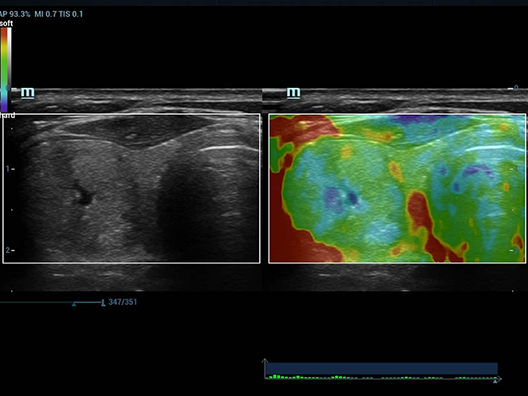

Fin dalla sua fondazione Mindray esplora continuamente nuovi modi per migliorare l'affidabilit├Ā diagnostica. Equipaggiata con la pi├╣ rivoluzionaria tecnologia ZONE Sonography?, la nuova piattaforma ZST+ di Resona 7 porta la qualit├Ā dell'immagine ecografica ad un livello superiore con l'acquisizione per zone e l'elaborazione dei dati canale.

Oltre alla qualit├Ā delle immagini di livello eccellente, Resona 7 migliora anche le capacit├Ā di ricerca clinica il rivoluzionario V Flow per la valutazione emodinamica vascolare, e l'acquisizione piani pi├╣ intelligente dal set di dati 3D per la diagnosi del sistema nervoso centrale fetale. Combinando il pi├╣ intuitivo funzionamento multi-touch basato su gesti e tutte le caratteristiche cliniche essenziali, Resona 7 sta veramente portando nuove tendenze nellŌĆÖinnovazione dellŌĆÖecografia.